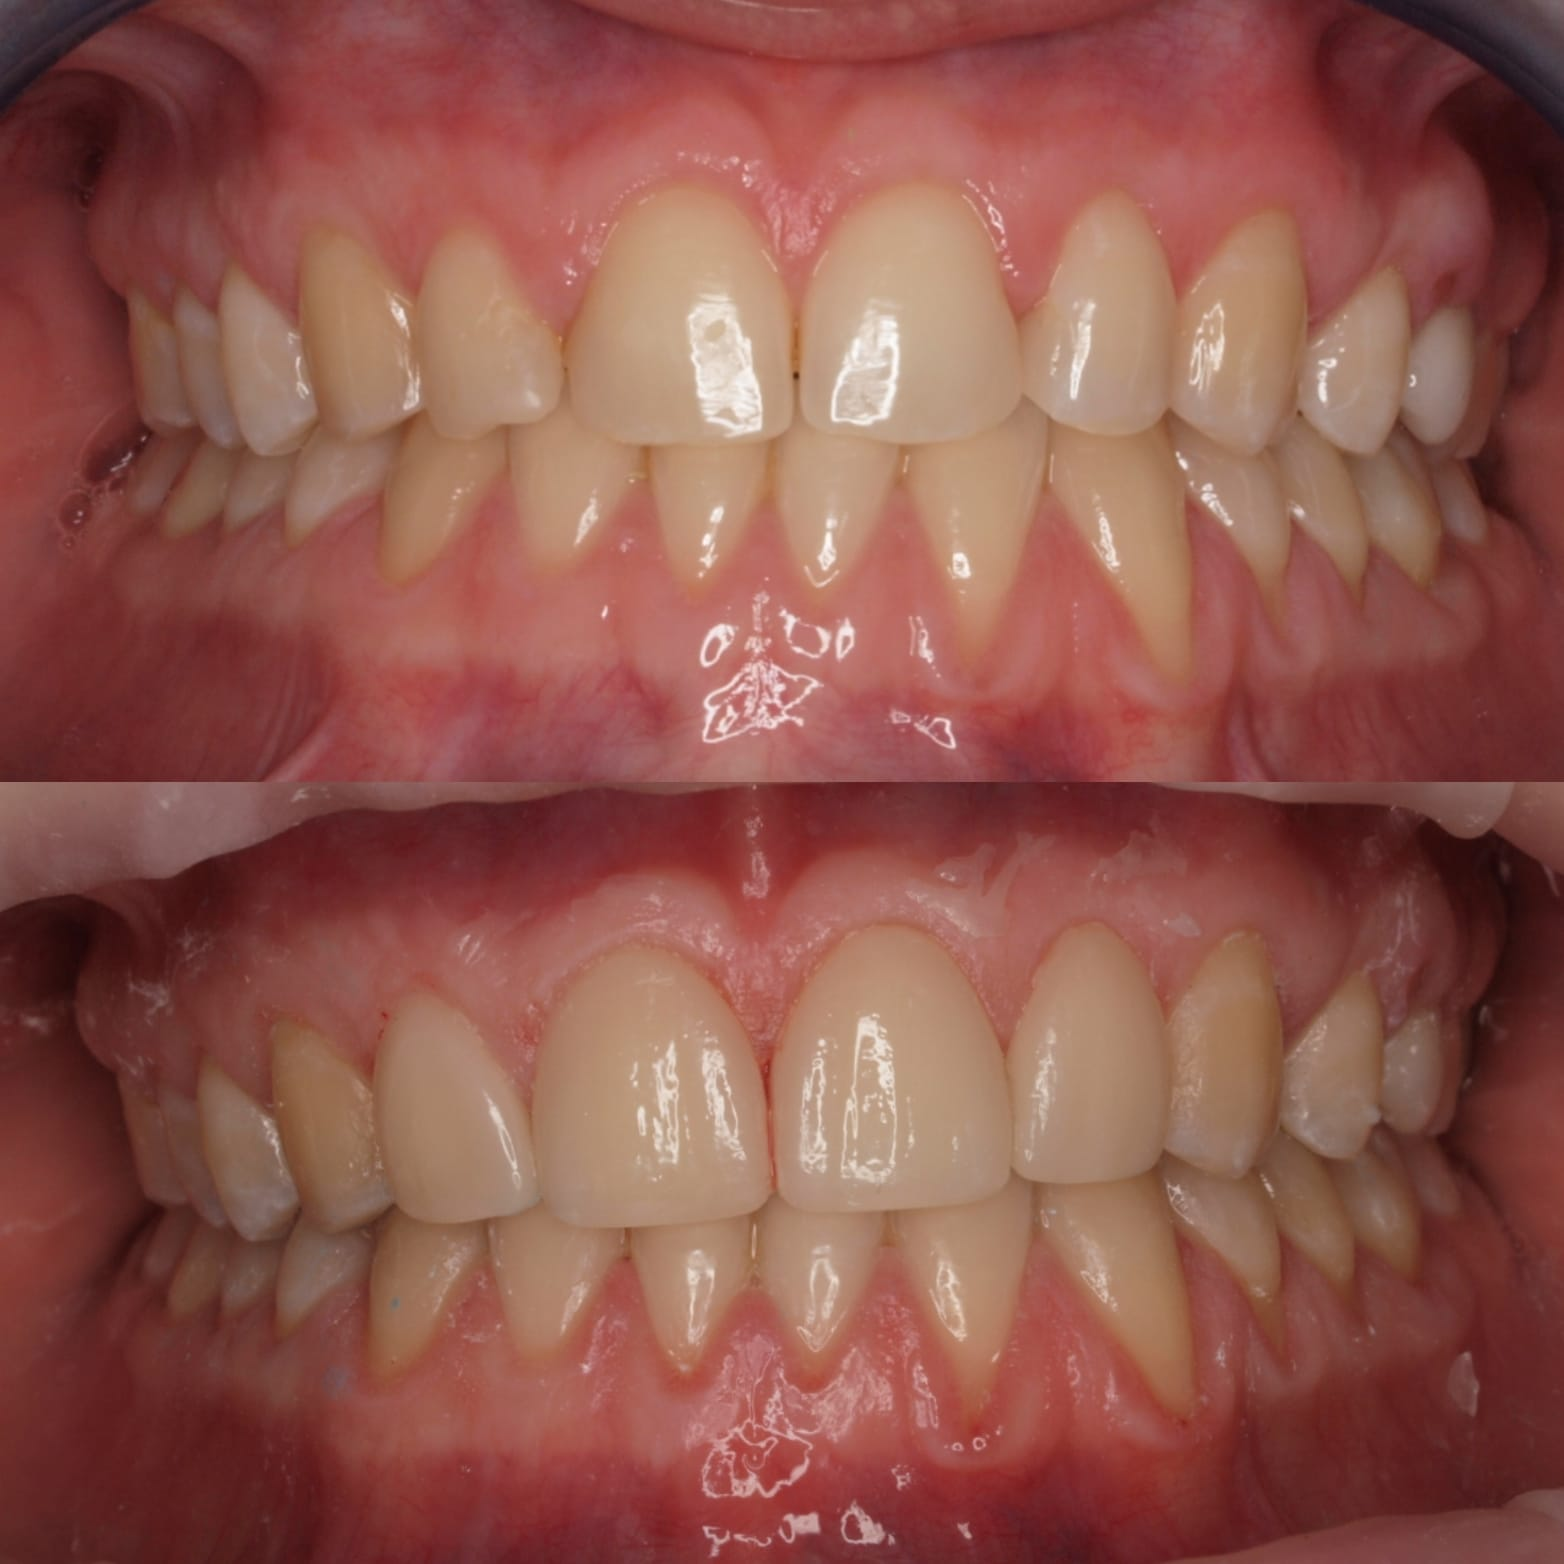

Casos de pacientes

En Clínica Dental Dr. Molinete trabajamos para que los procesos y las intervenciones sean lo más rápido y eficaz posible y con el mejor de los tratos. Tras 12 años de experiencia contamos con diferentes casos de pacientes resueltos de forma óptima.

Aquí te mostramos algunos de ellos.